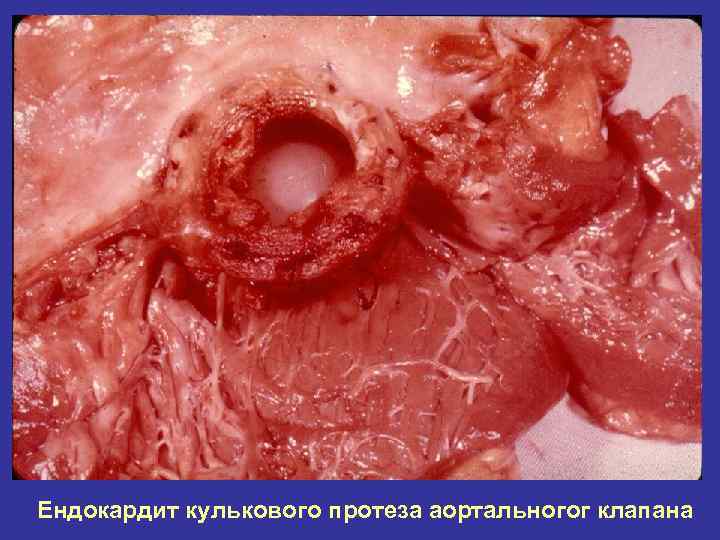

Ендокардит кулькового протеза аортальногог клапана

Протези клапана серця Св. Іуди з Біологічний протез клапана серця центральним током крові з фіксацією на опорному кільці, з обробкою біотканин і консервацією їх глутаровим альдегідом. аортальний мітральний дископодібний протез Кулеподібний протез